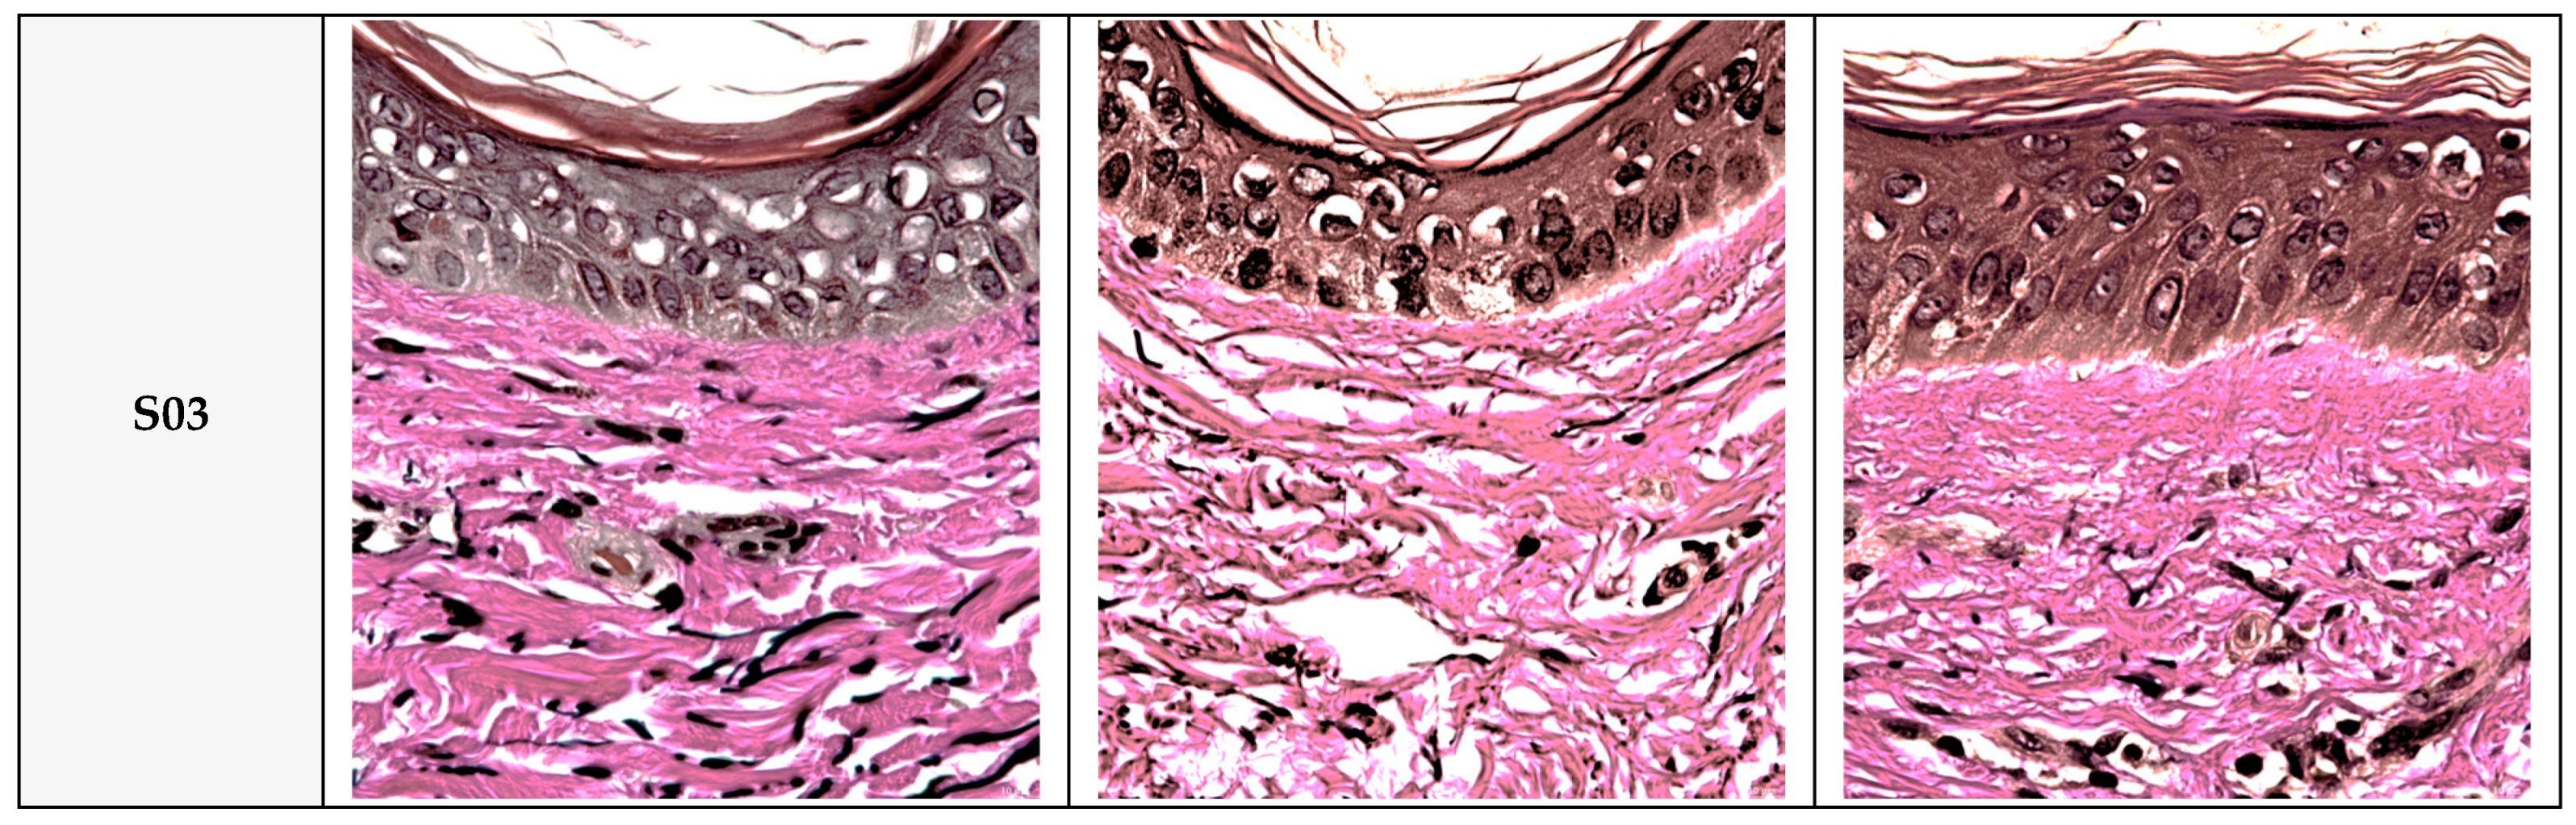

Protective effects of QC:HPN (8:1) on collagen structure in UVA-exposed human skin tissue (Masson’s trichrome staining, 400×). Representative images of human skin tissue cross-sections stained with Masson’s trichrome (MT) at 400× magnification. Tissues were divided into three groups: untreated negative control, UVA-irradiated vehicle control, and QC:HPN (8:1)-treated test sample (TS) group. In the vehicle group, UVA exposure resulted in significant collagen degradation and disruption of dermal architecture. In contrast, treatment with QC:HPN (8:1) preserved collagen fiber density and improved tissue structure. Collagen fibers are stained blue, keratin and cytoplasm are stained red, and nuclei are stained dark. S01–S03 represent tissue sections from three independent human donors.

Protective effects of QC:HPN (8:1) on elastin fiber structure in UVA-exposed human skin tissue (Verhoeff–Van Gieson staining, 400×). Representative images of human skin tissue cross-sections stained with Verhoeff–Van Gieson (VVG) at 400× magnification. Tissues were categorized into three groups: untreated negative control, UVA-irradiated vehicle control, and QC:HPN (8:1)-treated test sample (TS) group (5 µg/mL). VVG staining visualizes elastin fibers in black, collagen in red, and cytoplasm in yellow-pink. In the vehicle group, UVA exposure caused fragmentation and degradation of elastin fibers. In contrast, treatment with QC:HPN (8:1) preserved the continuity and organization of elastin fibers, indicating protection against UVA-induced elastin damage. S01–S03 represent skin samples from three independent human donors.

Histological Analysis: Masson’s trichrome staining (Figure 9) confirmed these biochemical findings, showing dense and organized collagen fibers in control skin, while UVA-exposed tissue exhibited fragmented and diminished collagen. TS maintained fiber density and organization similar to the control group. Similar findings are reported in studies using antioxidants to preserve dermal structure [18,76].

Verhoeff–Van Gieson (VVG) staining (Figure 10) revealed intact and well-aligned elastin fibers in the control group, which were significantly degraded after UVA exposure. In contrast, TS samples showed preserved elastin morphology, closely resembling the negative control. This mirrors results where polyphenols like EGCG prevent elastin fragmentation by reducing oxidative damage [73,75].

Overall, these results demonstrate that QC:HPN 8:1 formular effectively protects collagen and elastin fibers from UVA-induced damage, both quantitatively and histologically, supporting its role in maintaining dermal structural integrity under UV stress.